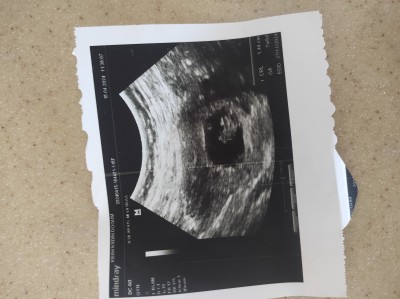

Elimde sekizinci haftanın ultrasonu var şuan 12 haftalık sizce keseden cinsiyeti nedir var mi tahmininiz

Çok küçük henüz.Allah gönlüne göre versin

Keseye göre kız canım

Kiz canisi benim keseye benziyor

Yok ben inanmam öyle şeylere ama iki kızım var iki kizimdaki kese de böyleydi o yüzden dedim kuzum erkek genelde fasulye gibi oluyor

Bence erkek sonucu öğrenince bizimle paylaşmanı bekliyorum hayırlısı olsun

Kiz bence de